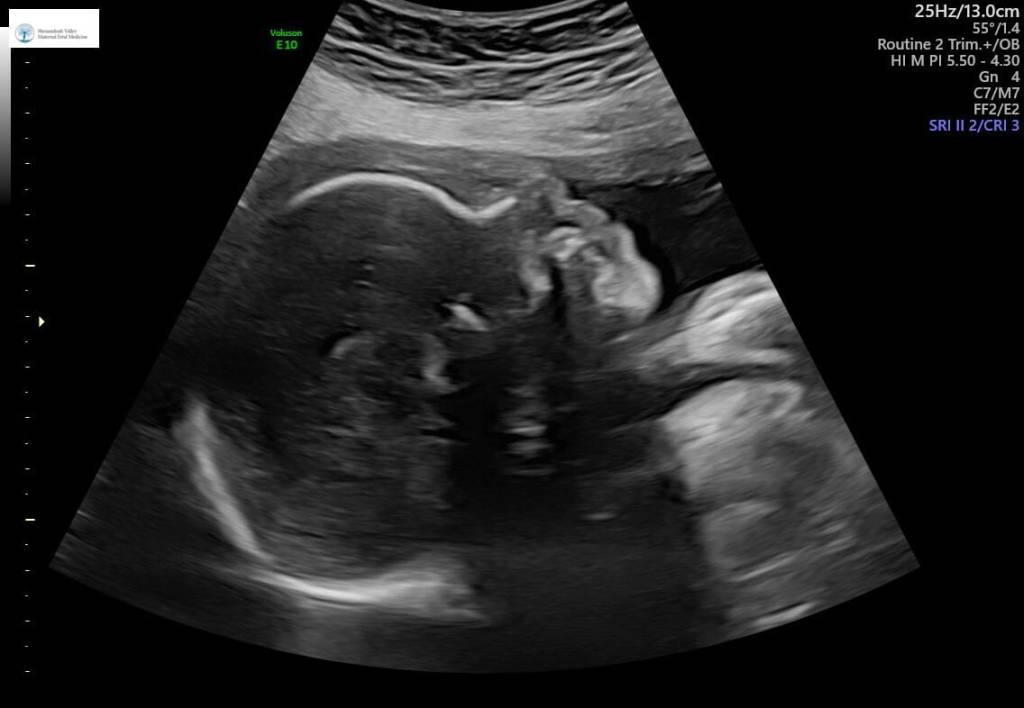

Within the next few weeks, I will be traveling on the earthly plane to visit my daughter in Virginia in order to be present for the arrival of a new grandson, and to share in the joy of participating in the activities taking place surrounding the appearance of a brand-new life in our extended family. These events, while clearly taking place in the temporal world and happening as a result of physical processes, point in the direction of a much deeper and more profound threshold of human existence. The technology surrounding the birth of children these days allows us a sneak peek into the miracle that is life.

Inside the tiny skull of this little miracle child, as is the case with all nominally functional developing babies, is a brain that is literally exploding with neurogenesis, (the creation of new neurons) and along with all the other vitally important developmental processes, must proceed along for a sufficient number of weeks in one of the most precarious situations that a human will ever face. The brain in particular requires such a delicate balance of nutrients and life support from the mother that diligent monitoring and optimizing of that environment is essential for a good result.